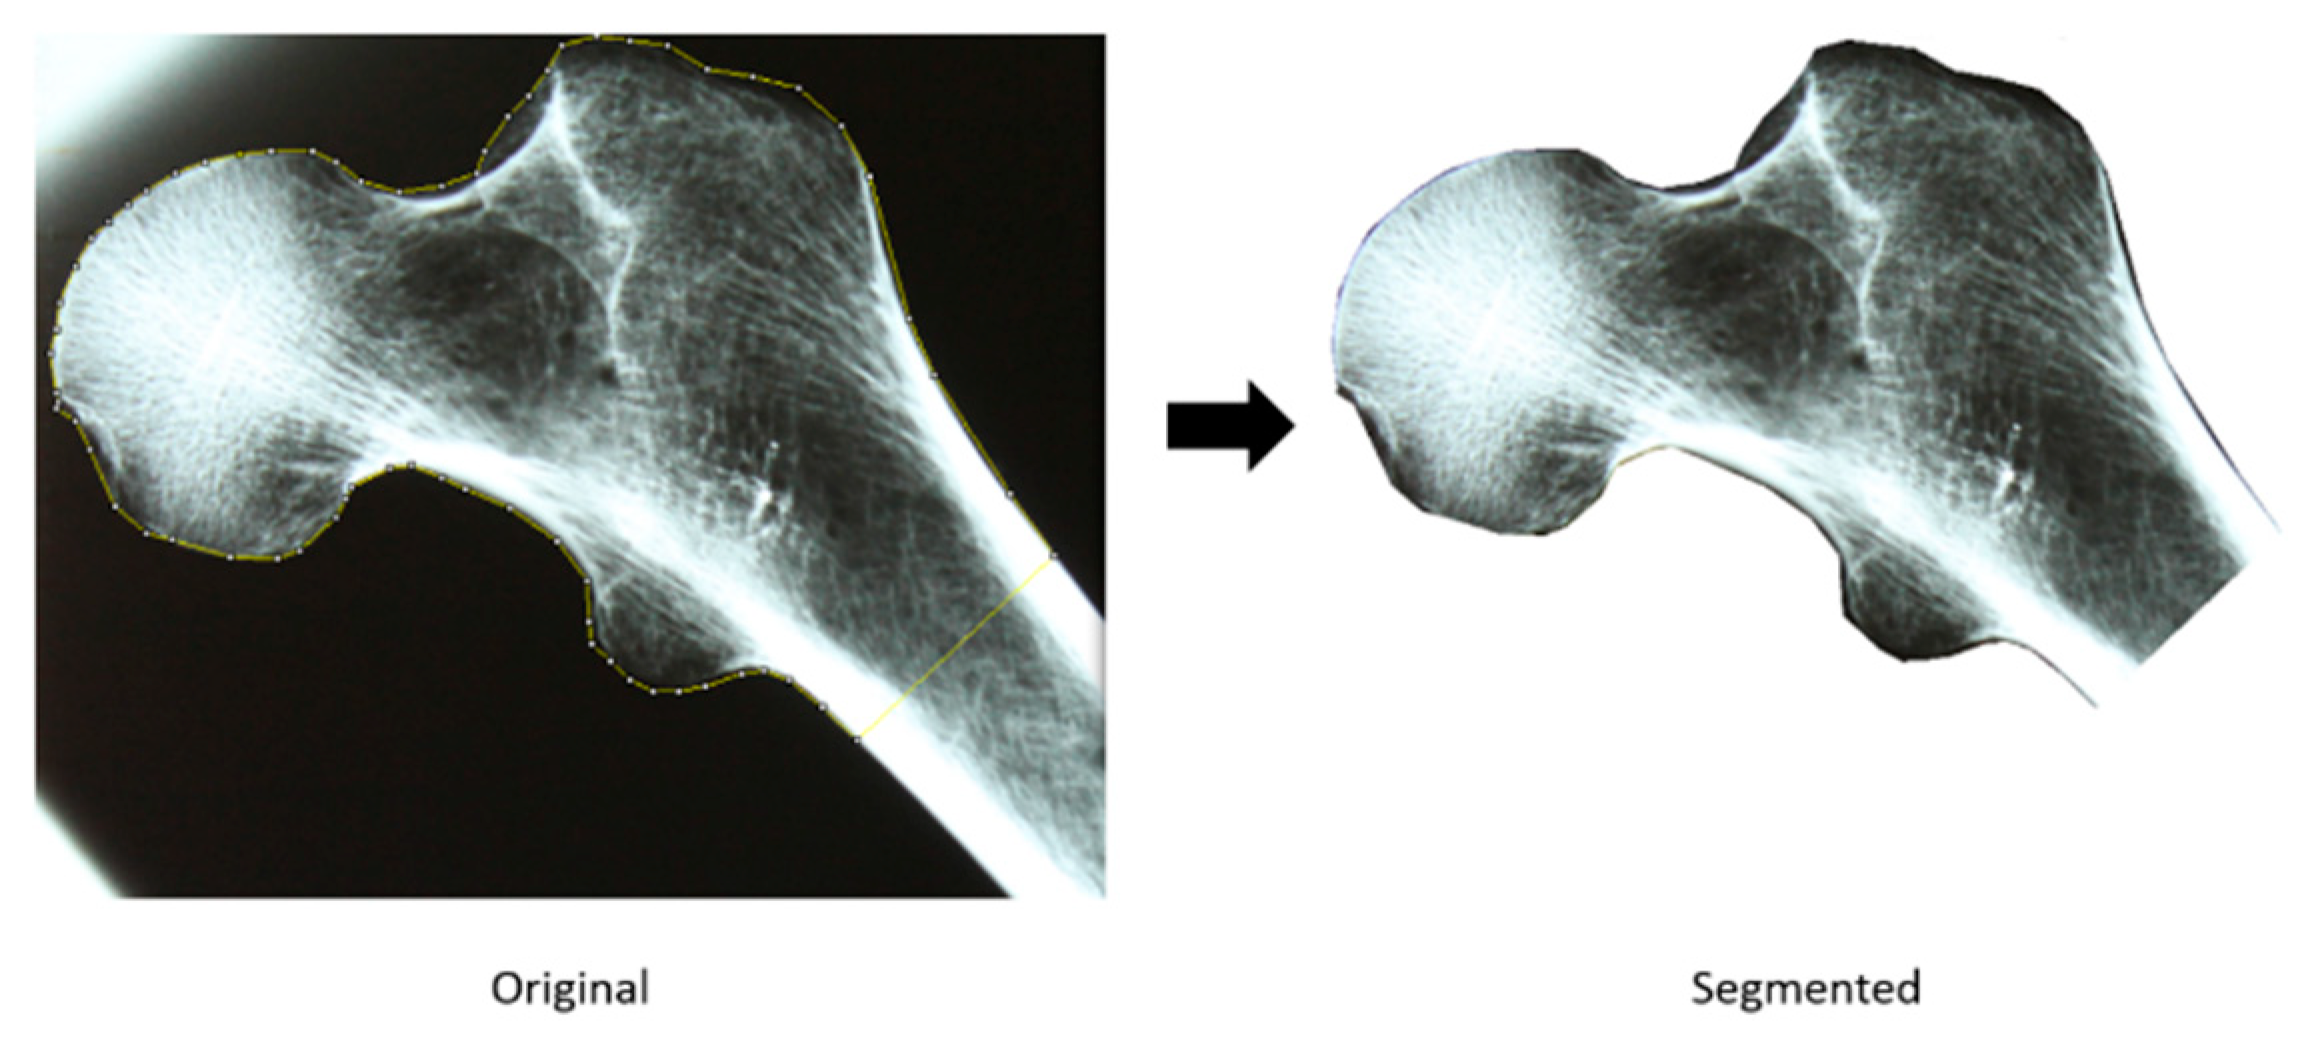

The first step to assess the utility of an image processing approach for automatic feature extraction and age estimation from the proximal femur was to produce a digital representation of the conventional X-ray films. All X-ray films were mounted in a light box and digitally acquired with a tripod-mounted DSLR camera (shutter speed: 6, aperture: f/5, focal length: 55 mm, automatic white balance, resolution: w [width] - 4272 by h [height] - 2848).

After image acquisition, all images were manually segmented with ImageJ software (National Institutes of Health and the Laboratory for Optical and Computational Instrumentation, University of Wisconsin) as illustrated in Figure 1. For a more precise and robust segmentation a polygon selection tool was used, and the region of interest was saved in a TIFF file of variable resolution. All subsequent analyses were conducted in the segmented regions only.

Figure 1. Feature extraction with Principal Components Analysis – a femora space and eigenfemora approach.